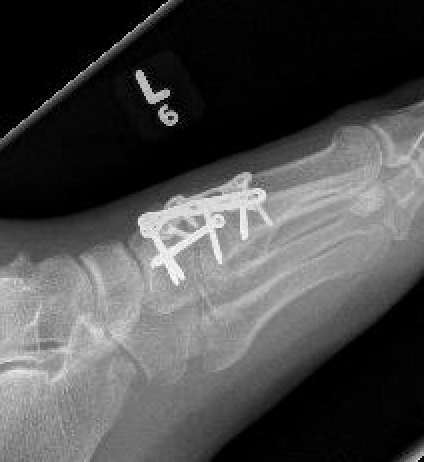

Screw versus bridge plating

- comparison of screw fixation versus bridge plating

- 60 ligamentous Lis Franc

- slightly better outcome scores at 2 years with bridge plate

- anatomic reduction: bridge plate 91%, screw 82%

Bridge plate

Bridge plate to 1st TMT and second TMT with Lisfranc screw